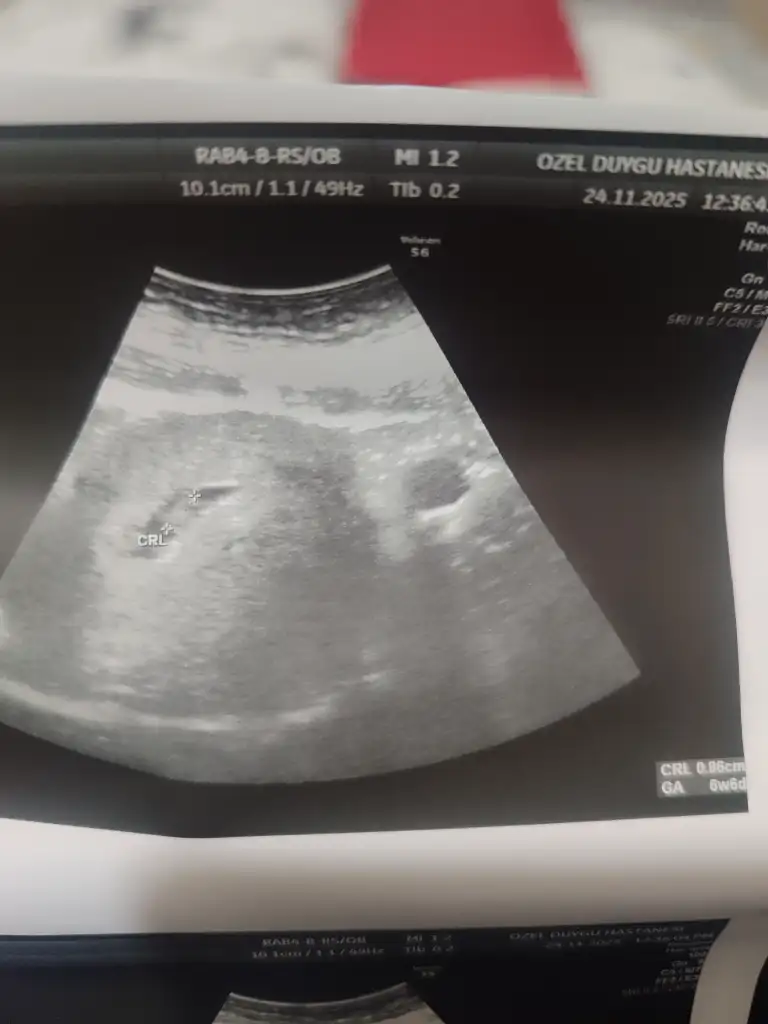

Cumartesi günü doktora gittim karından keseyi gördü 1.38 cm kese boş şuan gözükür diye düşünüyorduk haftaya pazartesi tekrar gideceğim![]()

Kaç haftalık bu görselleerGözükmez canım o boyutta bende 1.30 ken kese boyum görünmemişti doktor cok normal demişti ki 1 hafta sonra hem bebişi görmüştük hem kalp atısını dinlemiştik merak etme

Biri 6+1 diğeri 7+1 canımKaç haftalık bu görselleer